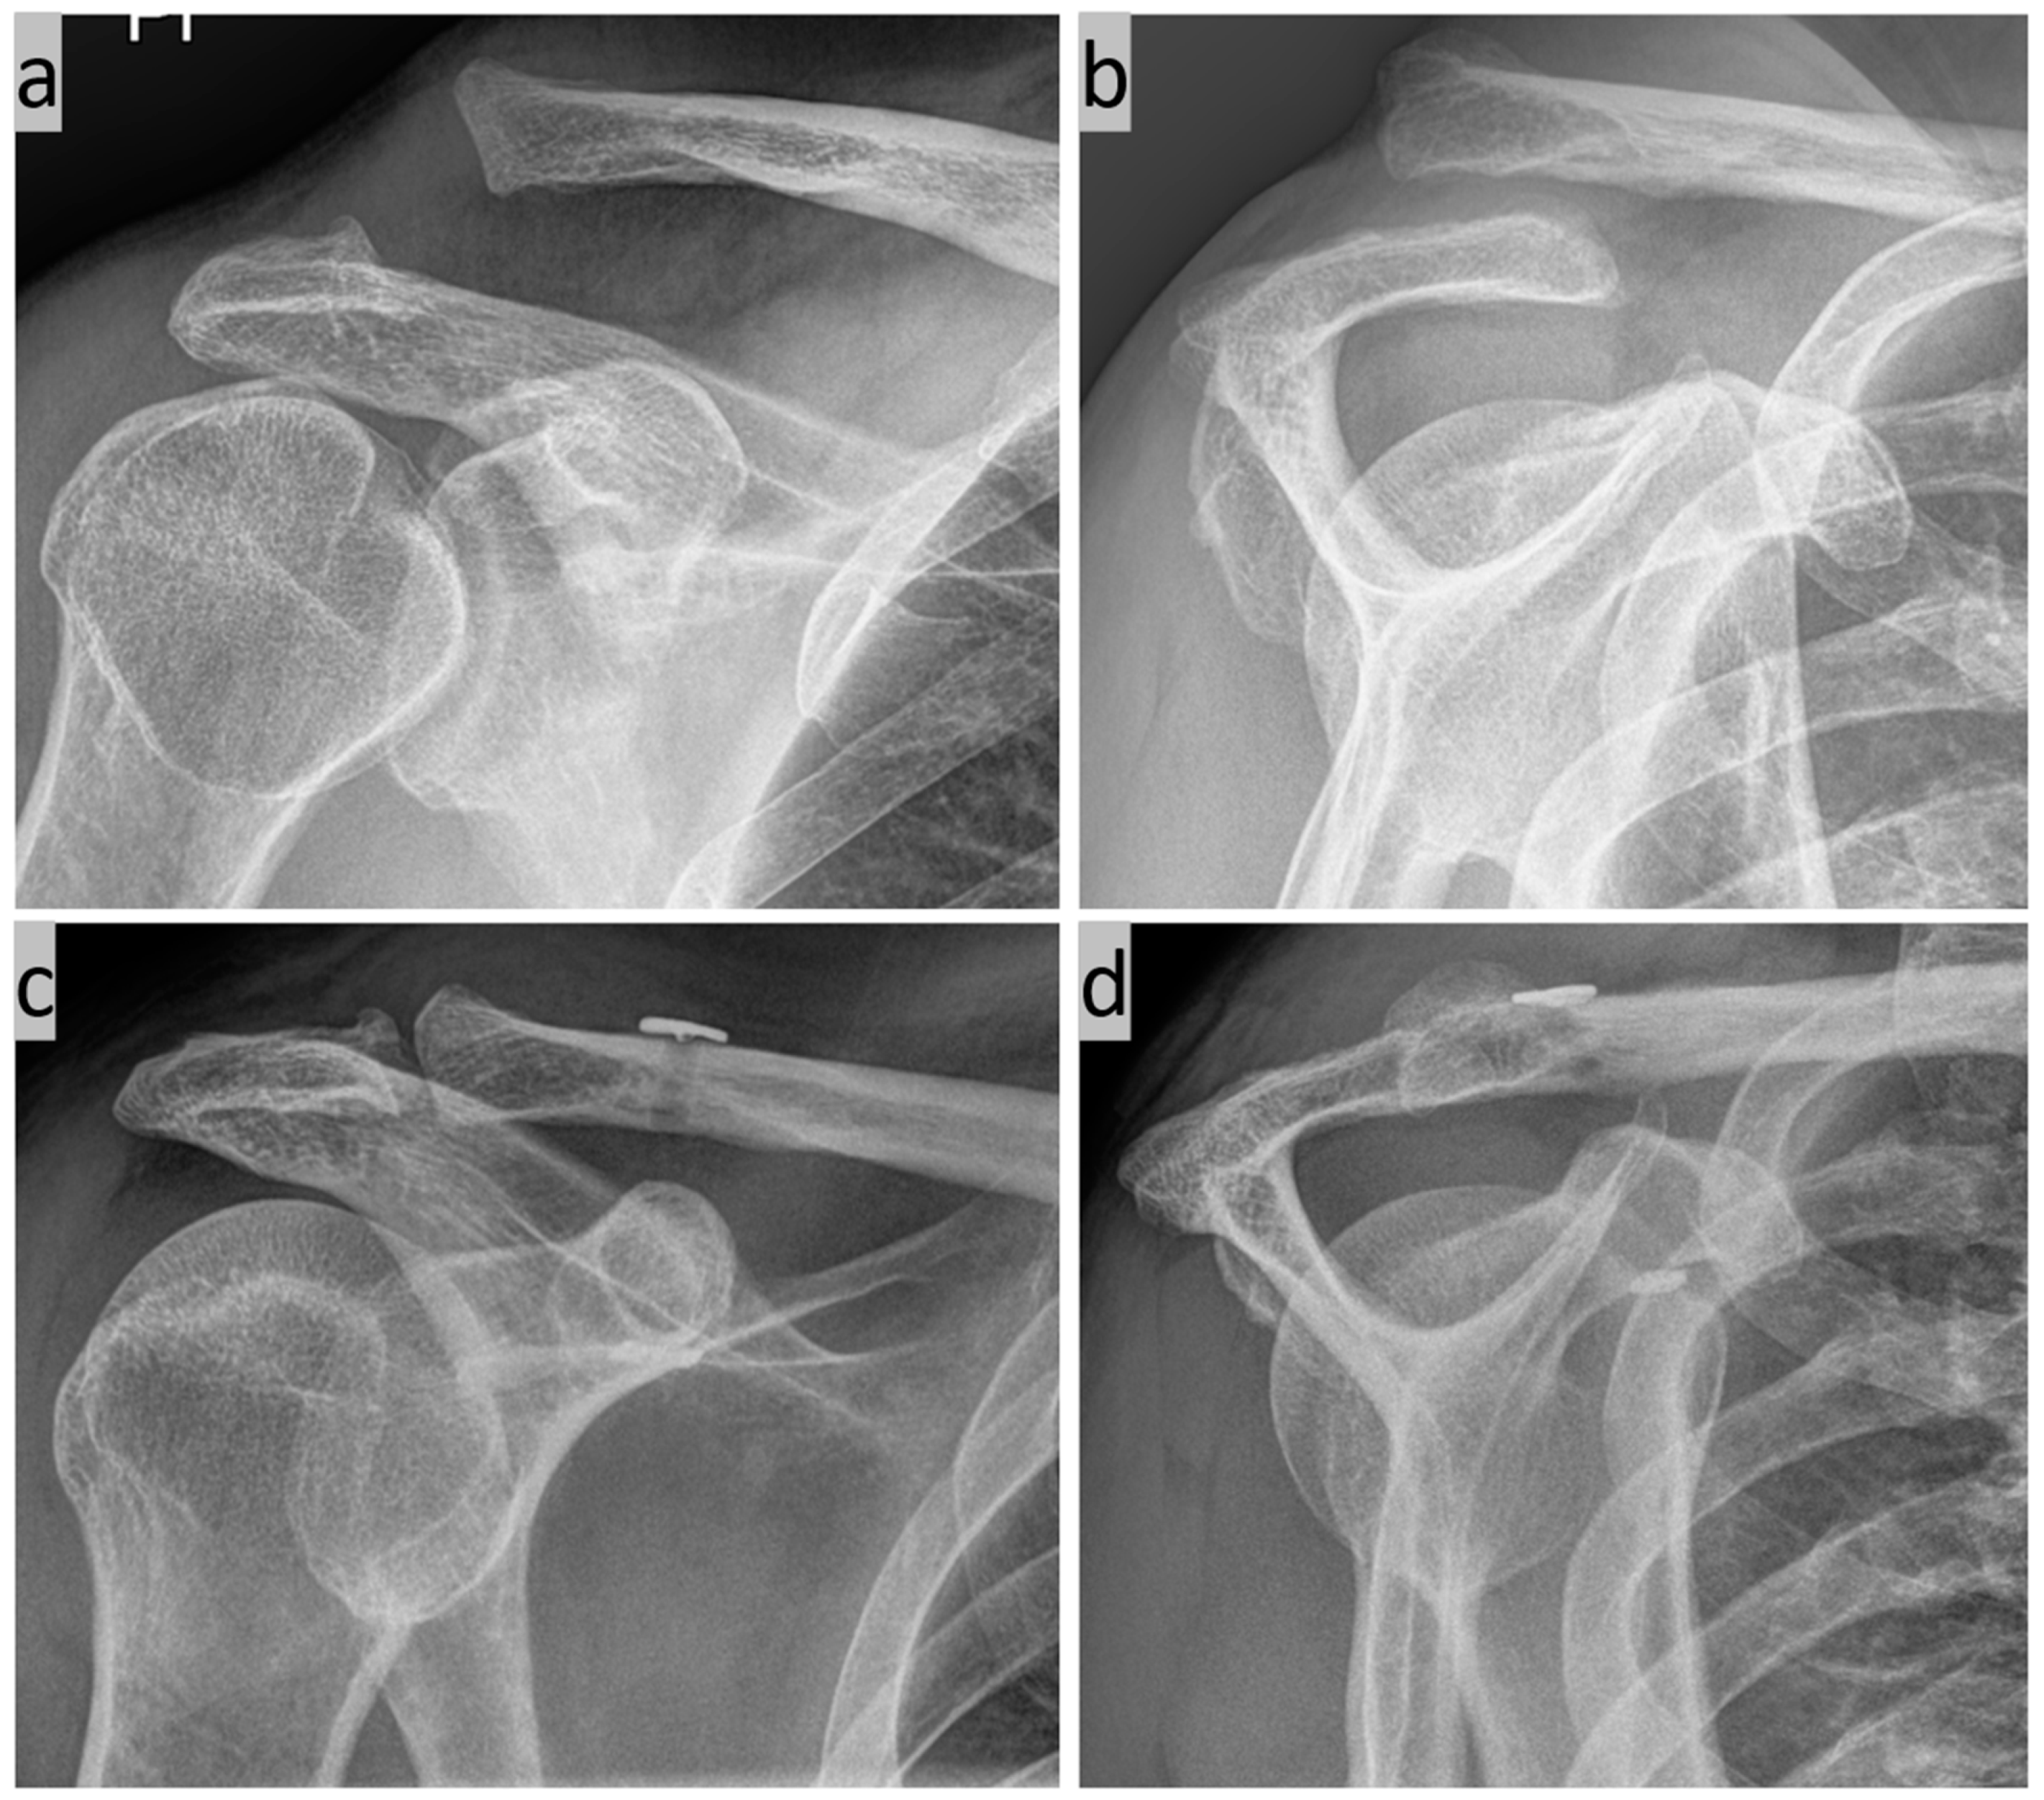

2. Surgical Technique